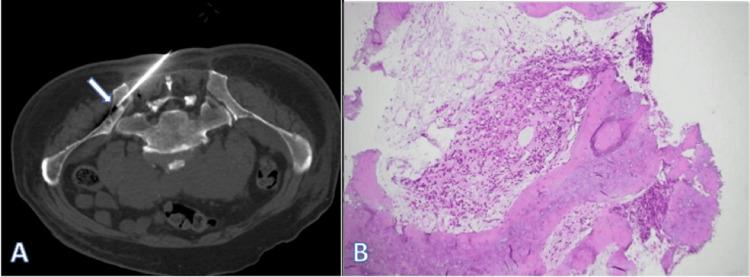

A Case of Rosai-Dorfman Disease Complicated by Bone Metastasis From Prostate Cancer.

Rosai-Dorfman disease (RDD) is a rare myeloproliferative disorder of histiocytes. The cause of the disease remains unclear. RDD mainly affects lymph nodes and has many extranodal manifestations, including the skin, lungs, eyes, and gastrointestinal tract. This report details a diagnostically challenging case where retroperitoneal lymphadenopathy initially suspected as metastatic prostate adenocarcinoma was pathologically confirmed as RDD. The concurrent occurrence of these two distinct pathologies underscores the importance of histopathological verification in atypical presentations, particularly for guiding precision oncology management.

罗萨伊-多夫曼病(RDD)是一种罕见的组织细胞增生性疾病。该病病因尚不清楚。RDD主要累及淋巴结,并有许多结外表现,包括皮肤、肺、眼和胃肠道。本报告详细介绍了一例诊断具有挑战性的病例,最初怀疑为转移性前列腺腺癌的腹膜后淋巴结病经病理证实为RDD。这两种不同病理情况的同时出现凸显了在非典型表现中进行组织病理学验证的重要性,特别是对于指导精准肿瘤学管理。